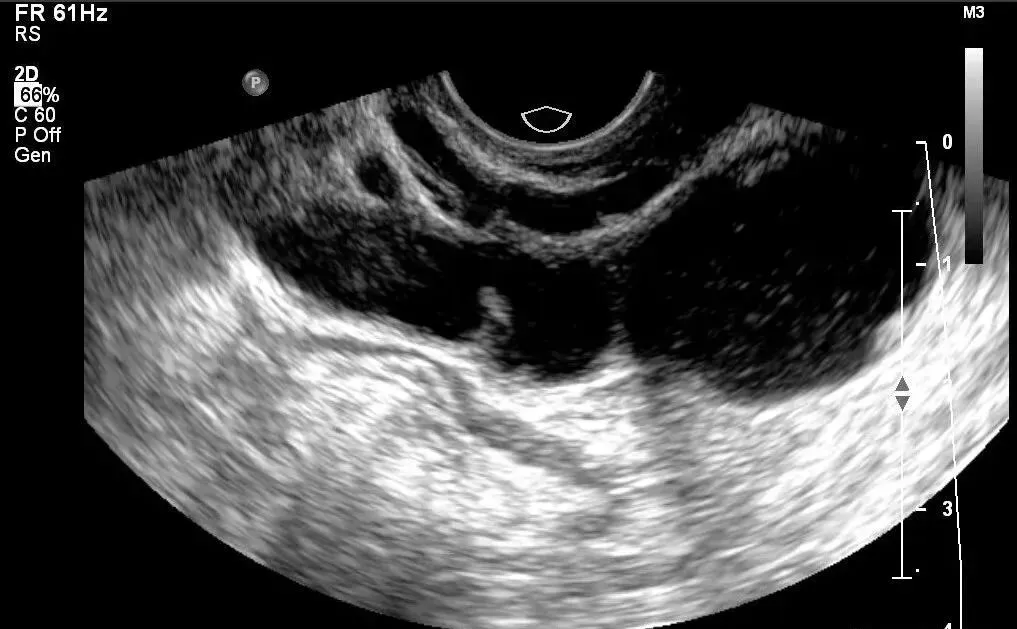

●声像图表现:宫腔内线性、圆形或三角形强回声。

●宫内节育器位置正常:节育器强回声位于宫腔中心,其周围内膜显示为低回声的晕圈。在子宫纵切面可判断宫内节育器在宫腔内的位置正常位置的宫内节育器应全部位于宫腔内,且节育器最下缘不低于宫颈内口。